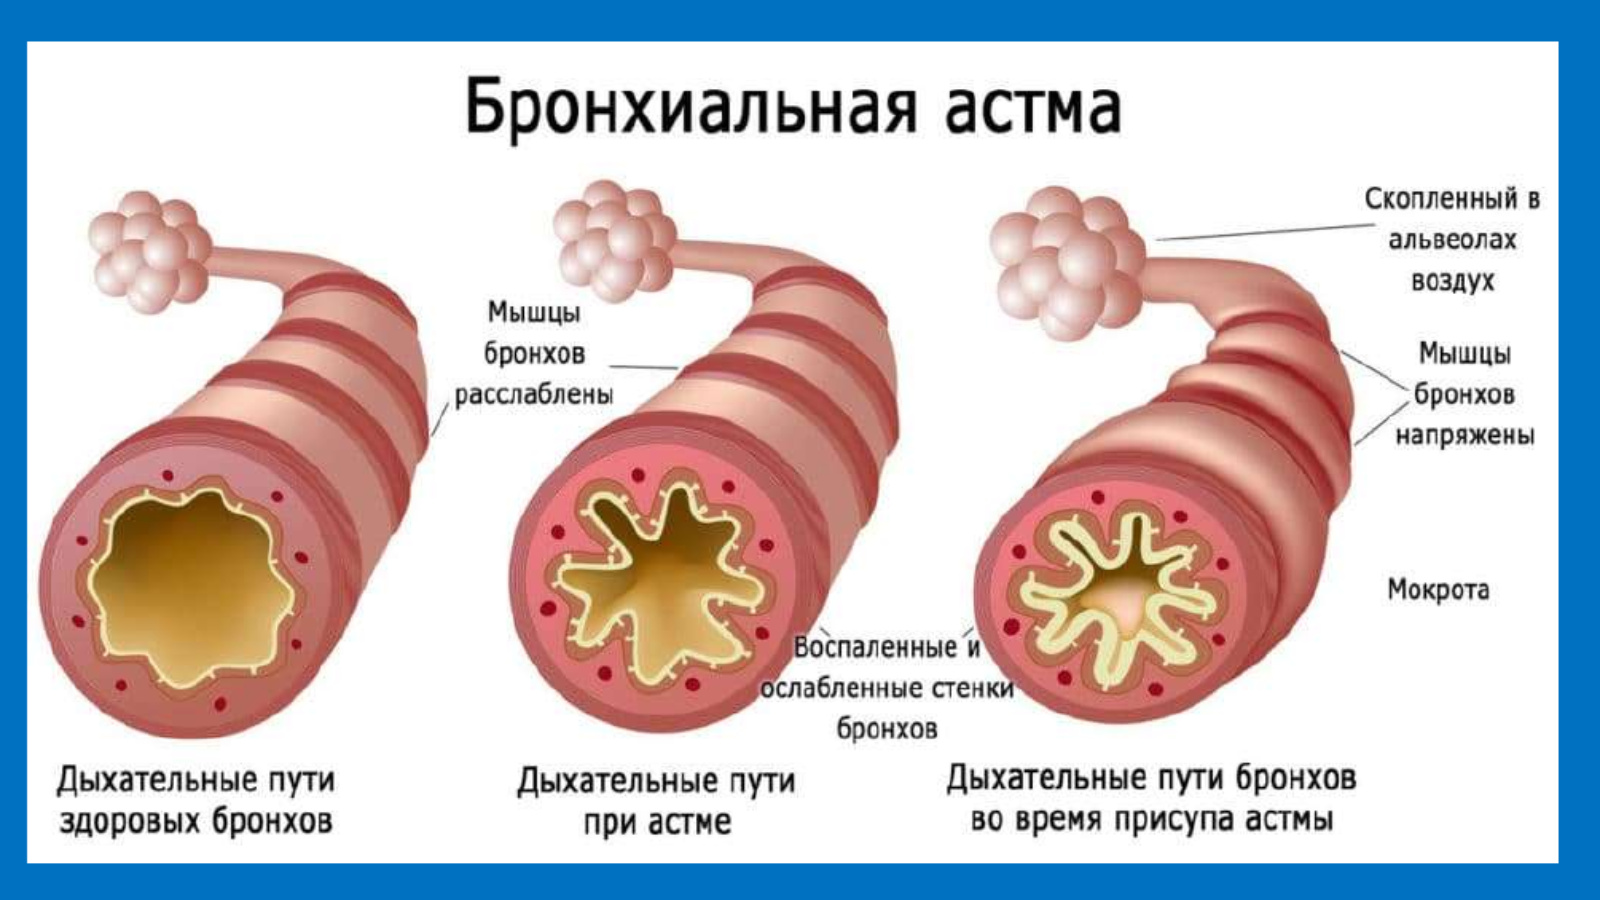

Эмоциональные фотографии: воздух легкий или тяжелый

Раздел: Точки зрения